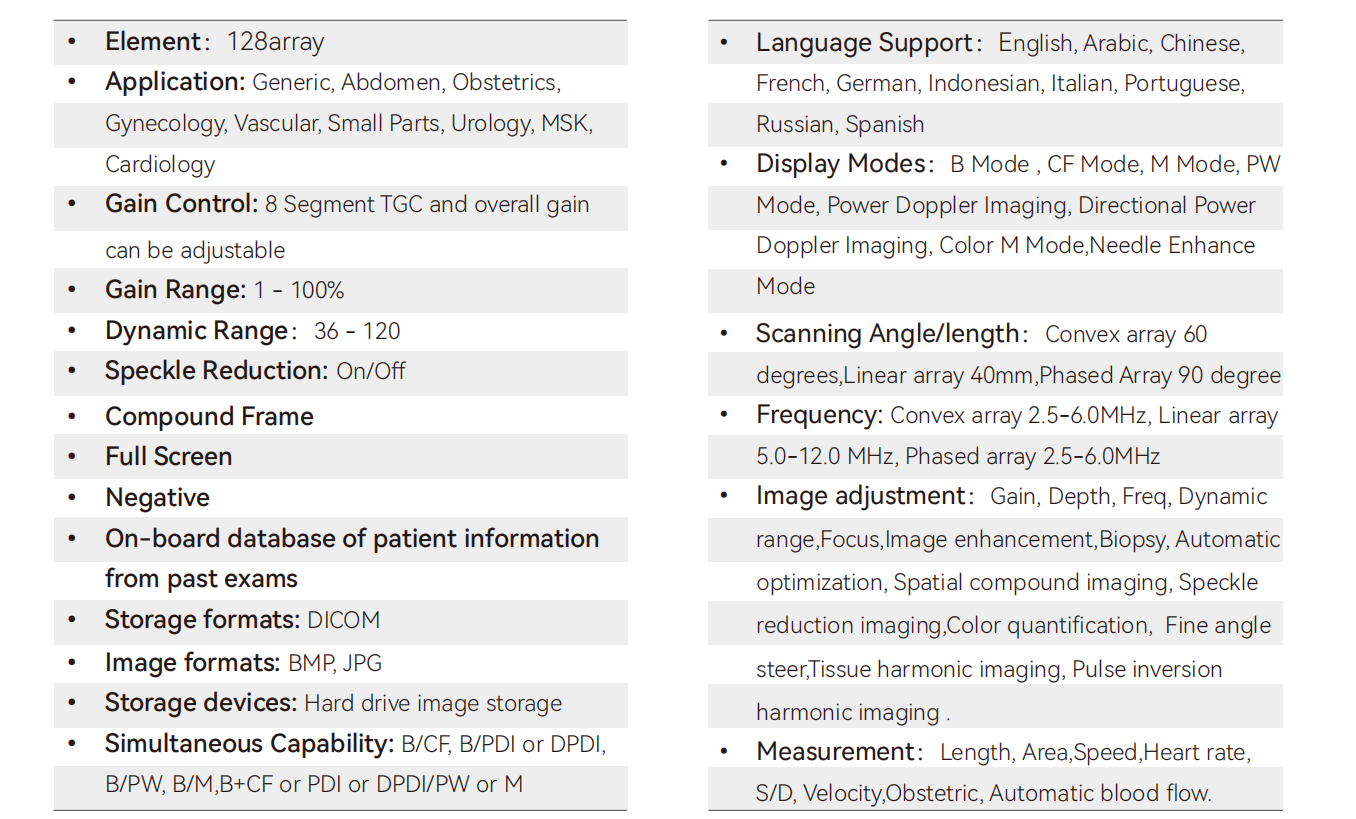

Carotid + CF + PW + Auto Trace

Carotid

Liver + CF

Cardiac + Color M

MSK

Thyroid + CF

Radial Artery + CF

Kidney